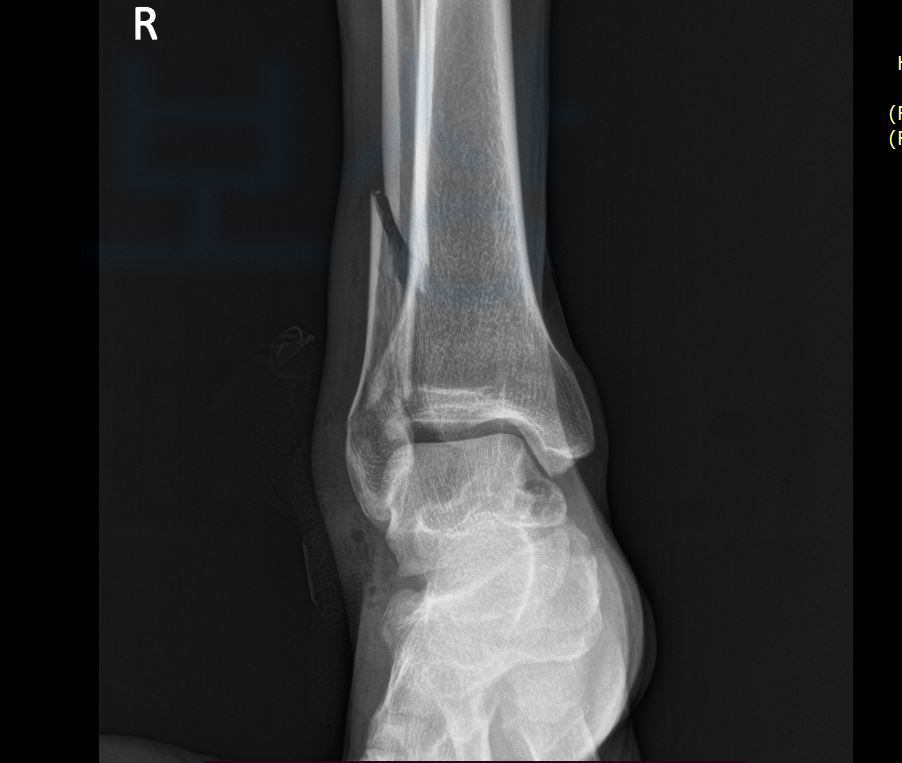

다만 비골과 거골 골절 수술 후 최대한의 치료를 시행했음에도 신체에 영구적으로 장해가 남을 수 있습니다.

이 경우 산재보험에서는 장해급여 항목으로 장해의 정도에 따라 등급을 지정해 보상해주는데요, 비골, 거골과 관련 있는 다리의 장해 산재 장해등급 기준은 아래와 같습니다. 다리의 기능장해 항목으로 장해 기준을 살펴보아야 하며

우리가 살펴 보아야 할 기준은 1개 관절의 장해가 단순 기능장해인지, 뚜렷한 기능장해인지 살펴보아야 하겠죠? 발목의 경우 산업재해보상보험법에 명시되어 있는 운동범위를 기준으로 3/4, 1/2, 1/4 순서대로 정도에 따라 등급이 나뉘게 됩니다.

따라서 올바른 장해 평가와 객관적인 각도 측정이 필수적인데요, 일부 병원에서는 장해평가에 생소하다보니 올바른 평가가 진행되지 못할 수 있습니다.